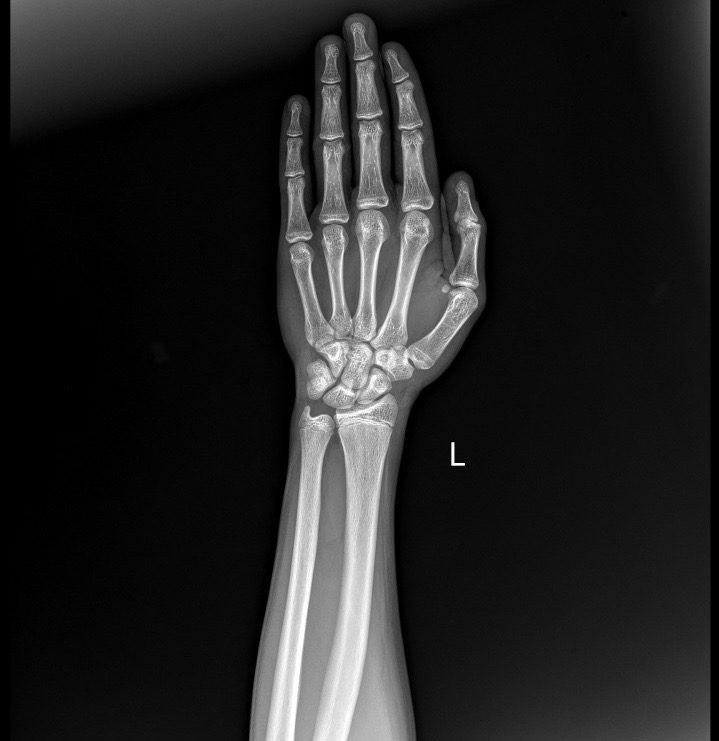

So make sure your plates are open before you take action

you can confirm this through an x-ray of your hand or knee

The younger your bone age, the more potential you have to grow

ideally it should be younger than 16, but even after that you could grow a few more cm